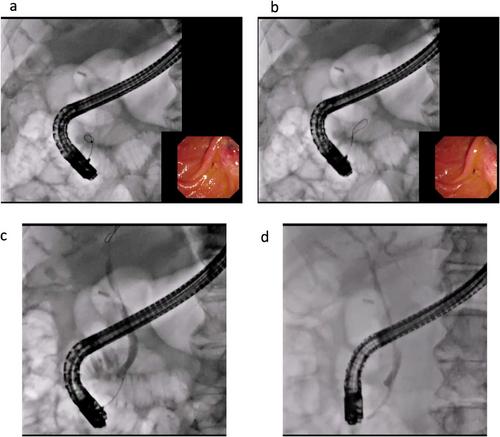

Wire-guided cannulation (WGC) reportedly increases the successful biliary cannulation rate and reduces the risk of post-endoscopic retrograde cholangiopancreatography pancreatitis. Currently, various types of guidewires are available. However, the effect of the length of flexible-tip guidewires on the success rate of biliary cannulation under WGC and the rate of adverse events, especially post-endoscopic retrograde cholangiopancreatography pancreatitis, is unclear. The aim of this study was to compare the influence of long-tapered and short-tapered tips of a 0.025-inch guidewire on outcomes in primary selective biliary cannulation.

Consecutive patients who underwent biliary access under endoscopic retrograde cholangiopancreatography guidance using WGC at 27 high-volume centers in Japan were enrolled in this prospective registration study. The primary outcome was the technical success rate of biliary cannulation. The secondary outcomes were the rates of adverse events, biliary cannulation time, and number of guidewire insertions into the pancreatic duct.

A total of 530 patients underwent biliary cannulation for biliary disease with native papilla between April 2021 and December 2023. The technical success rate of biliary cannulation was 86.1% (161/187) in the long-tip group and 84.3% (289/343) in the short-tip group, indicating no significant differences between the two groups. Although the frequency of post-endoscopic retrograde cholangiopancreatography was not significantly different, the successful biliary cannulation rate without guidewire mis-insertion into the main pancreatic duct was significantly higher in the long tip group (64.7%, 121/187) compared with the short tip group (54.2%, 186/343p = 0.02).

In conclusion, WGC using long-tip guidewires might reduce the risk of guidewire insertion into the main pancreatic duct.